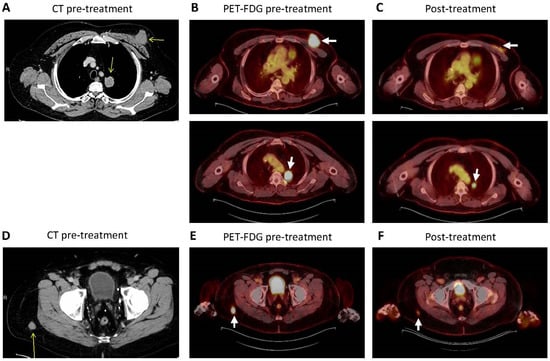

Case Report

Extranodal NK/T-Cell Lymphoma, Nasal Type, Presenting as an Isolated Oral Manifestation

by Andrea Kanizsai, Ágnes Bán, László Kereskai and Árpád Szomor

Dent. J. 2026, 14(2), 129; https://doi.org/10.3390/dj14020129 - 23 Feb 2026

Background/Objectives: Extranodal NK/T-cell lymphoma, nasal type (ENKTCL-NT), is a rare and extremely aggressive subtype of non-Hodgkin lymphoma that most frequently involves the nasal cavity and upper aerodigestive tract. Primary isolated oral manifestation is exceptionally uncommon and may mimic odontogenic or infectious diseases, [...] Read more.

Background/Objectives: Extranodal NK/T-cell lymphoma, nasal type (ENKTCL-NT), is a rare and extremely aggressive subtype of non-Hodgkin lymphoma that most frequently involves the nasal cavity and upper aerodigestive tract. Primary isolated oral manifestation is exceptionally uncommon and may mimic odontogenic or infectious diseases, delaying diagnosis. We report a case of ENKTCL-NT presenting initially as a destructive oral lesion without sinonasal involvement at diagnosis. Methods: A 32-year-old man with progressive palatal ulceration underwent clinical and imaging assessment (panoramic radiography and staging ^18F-FDG PET–CT) and repeated biopsies. Diagnosis was established using histopathology (H&E), immunohistochemistry (T-cell markers and cytotoxic profile), EBV detection by EBER in situ hybridization, and T-cell receptor gamma (TCRG) gene rearrangement analysis. Results: The lesion presented as a hemorrhagic, ulcerative palatal destruction covered by pseudomembranous exudate and was complicated by fungal infection, periostitis, and severe dental inflammatory foci, contributing to diagnostic delay. Histopathological examination revealed extensive necrosis with a dense atypical lymphoid infiltrate; angiocentric and angiodestructive growth was identified in one biopsy specimen. Tumor cells expressed T-cell markers (CD2, CD3, CD5, CD7; heterogeneous) and cytotoxic markers (TIA-1) and showed CD30 and CD56 positivity, with EBV positivity confirmed by EBER in situ hybridization. Molecular analysis demonstrated monoclonal TCRG rearrangement, and Ki-67 indicated high proliferative activity. Initial PET–CT demonstrated an intensely FDG-avid, locally invasive lesion without distant organ involvement. The patient was treated with L-asparaginase-based SMILE chemotherapy followed by radiotherapy (50 Gy), achieving marked initial clinical improvement and partial metabolic response; however, systemic relapse subsequently occurred with refractory disease despite salvage therapy and immunotherapy. Conclusions: This case highlights the substantial diagnostic challenge posed by isolated oral extranodal NK/T-cell lymphoma, nasal type, which may closely mimic benign inflammatory or infectious conditions and lead to significant diagnostic delay. Persistent, progressive, or therapy-resistant oral ulcerations should prompt early consideration of hematologic malignancy. Timely biopsy with comprehensive immunophenotyping, EBV testing, and close multidisciplinary collaboration are essential for accurate diagnosis and may contribute to earlier diagnosis and improved patient outcomes in these rare and atypical presentations. Full article